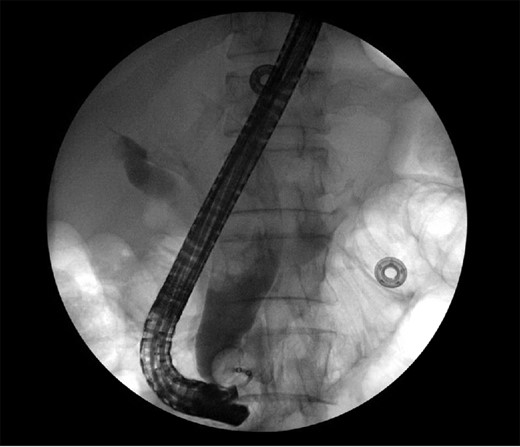

The patient is a 63-year-old Chinese male who presented with lethargy, 10-pound weight loss and painless jaundice for 1 week. Patient had a prior episode of jaundice of unclear etiology 2 years prior treated medically and had just emigrated from China 1 month prior to admission. Patient was febrile to 102.4°F, jaundiced with a total bilirubin of 18.5 mg/dL. Abdominal ultrasound showed intra and extrahepatic bile duct dilation, the distal CBD was dilated to 25 mm. Patient underwent endoscopic retrograde cholangiopancreatography (ERCP), which showed thick yellow mucus and no stones (Fig. 1). A sphincterotomy was performed and a pigtail stent placed. Computed tomography (CT), magnetic resonance imaging and magnetic resonance cholangiopancreaticogram failed to show a pancreatic head mass, distal CBD mass or stones causing obstruction (Fig. 2). Cold forceps biopsy of the papilla, endoscopic ultrasound with fine needle aspiration biopsy (FNAB) of pancreatic head, and CBD brushings were all nondiagnostic. CBD stents occluded two times in 2 weeks’ time secondary to thick mucus, requiring multiple ERCPs with stent exchanges (Fig. 3). After extensive multidisciplinary discussions regarding unclear etiology of distal CBD obstruction and extensive discussion with patient and family, the decision was made to perform a Whipple procedure for diagnosis and definitive treatment. Intraoperatively, choledochoscopy was performed, which showed very thick yellow mucus and frond-like mucosa near the ampulla. Final pathology showed a 2.0 × 1.5 × 0.5 cm3 granular lesion in the distal CBD. There was prominent biliary epithelial proliferation with tubular–papillary architecture and minimal nuclear atypia in association with chronic inflammation, stroma reaction and smooth muscle proliferation. The overall histological change in the distal CBD resembled that of AH seen in gallbladder, likely non-neoplastic change (Figs 4 and 5). At 1 year follow-up, he is doing well and his jaundice has resolved.